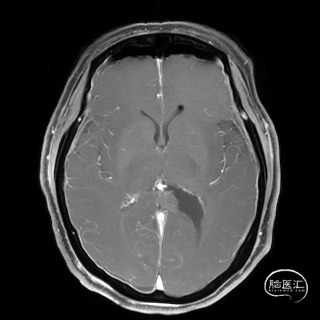

2023.04.21外院MR

术后影像

术后磁共振

术后患者神志清楚,无失语,无视力视野等神经功能障碍。